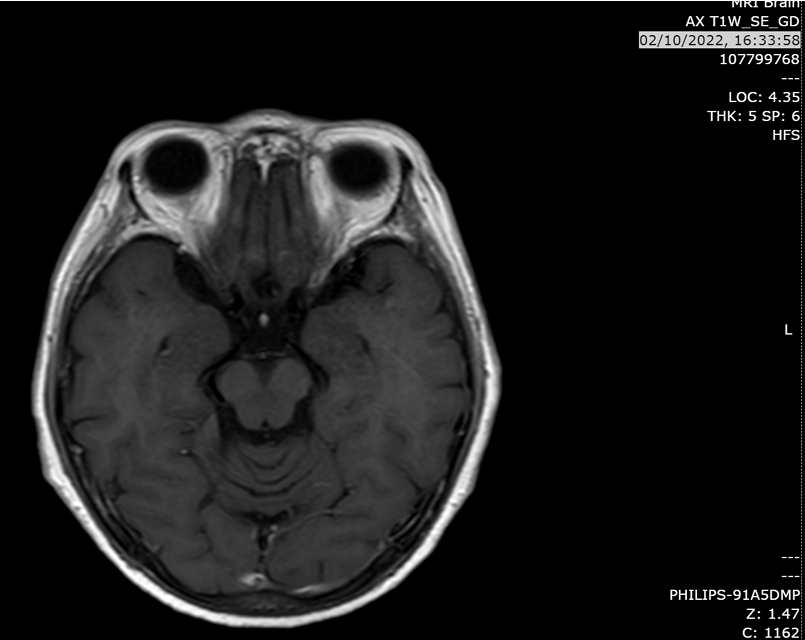

头颅MRI(2022-10-2):脑轴位T1增强扫描未见脑转移灶。